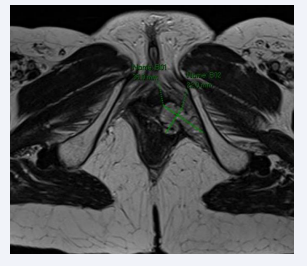

Figure 2: Pelvic MRI with constrast showing ovoidal lesion 33 x 16 mm.